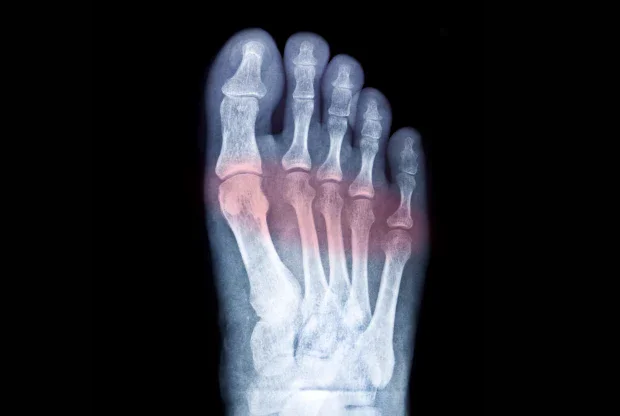

Поставянето на диагнозата метатарзалгия става след снемане на подробна анамнеза и осъществяване на щателен физикален преглед. Извършват се някои образни и лабораторни изследвания, като рентгенография, магнитен резонанс и компютърна томография за уточняване локализацията и тежестта на уврежданията.

- Рентгенография - има за цел да визуализира костни деформации, дегенеративни изменения на ставите и стрес фрактури